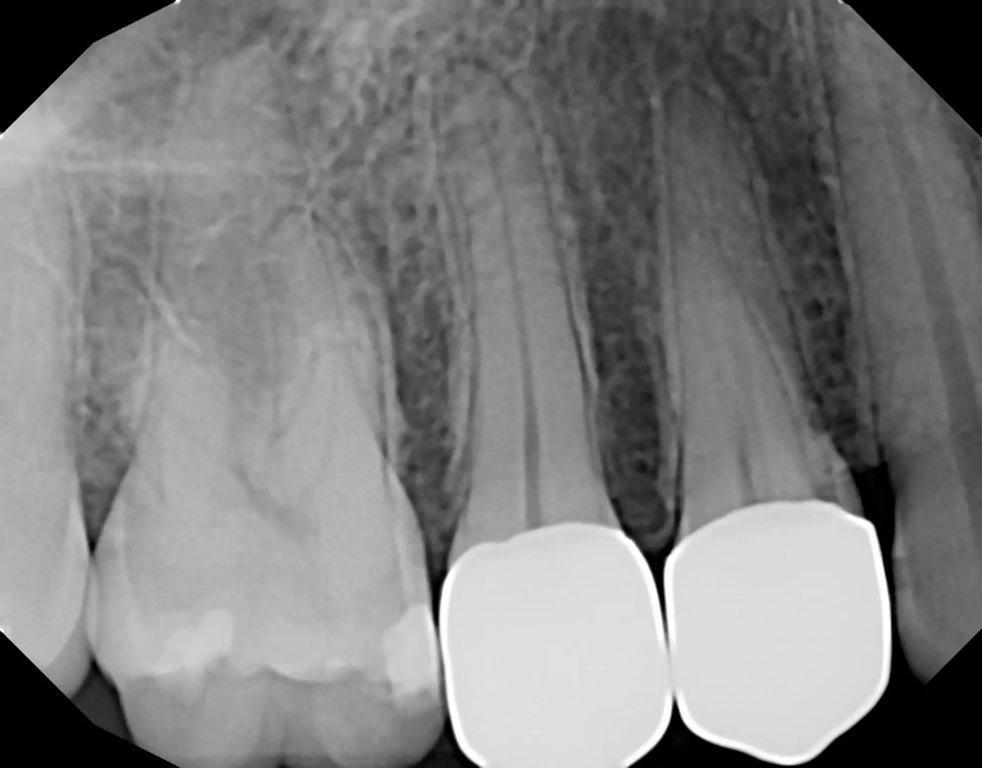

57-летний пациент обратился с жалобами на повышенную чувствительность к температуре в левом квадранте верхней челюсти. Был сделан рентгеновский снимок (фото 2), на котором был отмечен глубокий кариес на втором премоляре с возможным вовлечением пульпы. Периапикальная патология рентгенологически не была отмечена. Чтобы убедиться в жизнеспособности пульпы зуб подвергли испытанию холодом (фриз-тест). При проведении фриз-теста была отмечена слабая реакция, которая немедленно прошла, когда холод был удален с зуба, что указывало на то, что зуб был жизненно важным. Пациенту сообщили, что может потребоваться эндодонтическое лечение, если в результате удаления кариеса произойдет значительное обнажение пульпы или у зуба появятся симптомы после лечения. Если обнаруживается небольшое обнажение пульпы или в результате удаления кариеса дентин над пульпой становится тонким, перед установкой культевой вкладки следует провести лазерную обработку, чтобы стерилизовать область и избежать развития пульпита. Для этого зуба планировалось установить культевую вкладку и полную коронку. Пациент принял рекомендации по лечению.

Фото 2: Периапикальная рентгенограмма зуба №25, на которой виден кариес в непосредственной близости от пульпарной ткани.